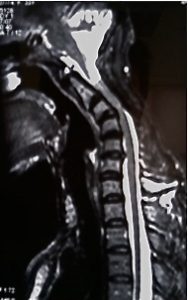

Cifosis postquirúrgica. Al retirar los elementos posteriores (arco posterior y complejo ligamentoso) se genera un desequilibrio entre musculatura extensora y flexora causante de la deformidad. En esta imagen de RM se aprecia la compresión de canal provocada por la retracción de los tejidos.